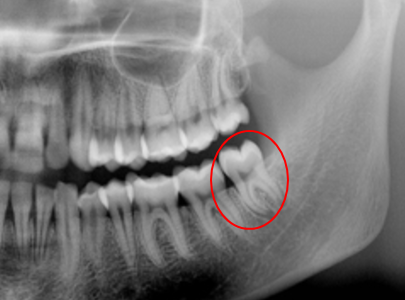

親知らずの抜歯は、その親知らずの生え方により難易度が異なります。

水平埋伏の親知らずの抜歯

水平埋伏歯とは、横向きに生えている歯のことをいい、抜歯の難易度はかなり高くなります。埋まっている親知らずを抜くため、歯茎を切開して埋伏している歯の一部分を露出させます。それから、歯を小さく分割しながら取り出します。歯の大部分が骨に埋もれている場合は、親知らずを囲んでいる骨の形を整えます。